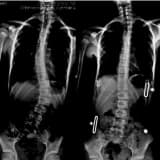

Yetkinlərdə skolyozun cərrahi müalicəsi

Müalicə xəstənin şikayətlərinə uyğun olaraq aparılır. Cərrahi müalicələrə dekompressiya, korreksiya və stabilləşdirmə müdaxilələri və ya bunların kombinasiyası daxil ola bilər. Cərrahi müdaxilələr kifayət qədər mürəkkəbdir və prosesin idarə edilməsi xəstənin yaşı, müşayiət olunan xəstəliklər, birləşmənin uzunluğu, bitişik seqmentlərin vəziyyəti, lumbosakral birləşmə, osteoporoz, əvvəlki cərrahi müdaxilələr və uzun müddət davam edən bel ağrısı və əzələ balanssızlığı ilə müəyyən edilir. Neyrogen klaudikasiya şikayətlərini aradan qaldırmaq üçün dekompressiya cərrahiyyəsi yaxşı seçimdir. Füzyon cərrahiyyəsi əyriliyin irəliləməsini dayandırmaq üçün istifadə olunur. Sagittal balanssızlığı və fırlanma deformasiyalarını aradan qaldırmaq üçün birləşmə ilə birlikdə alətlərə üstünlük verilə bilər. Degenerativ bel skolyozu olan xəstələrin cərrahiyyəsində tez-tez dekompressiya ilə yanaşı füzyon əməliyyatı da əlavə edilməlidir.

Adolesan deformitelerde eğriliğin büyüklüğü cerrahi endikasyonlarda önemli rol oynamasına rağmen yetişkinlerde ağrı ve fonksiyon bozukluğu, omurganın dejenerasyon ve denge bozukluğu ile korelasyon göstermektedir. Omurga patolojisinin sınırlı olduğu olgularda eğrilikte selektif füzyon uygulanabilirken yaygın segment hastalığında tüm eğrilik füzyona dahil edilmelidir. Sagittal ve /veya koronal planda dengesi bozulmuş olgularda ise her 3 kolonu içeren osteotomi ameliyatları iyi bir seçenek oluşturur.